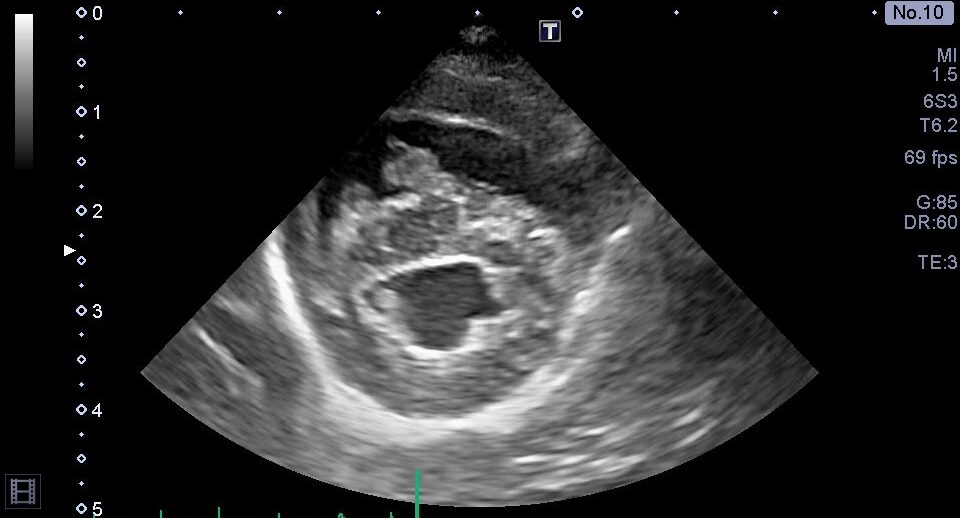

右心系の拡大

心室中隔の扁平化

胸部超音波検査では、上記のような肺高血圧症による心臓の変化が認められました。